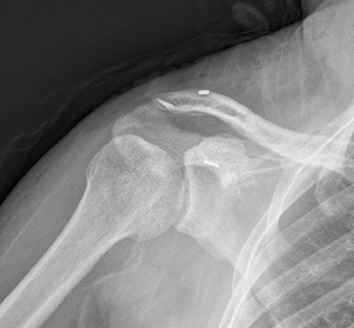

肩锁关节脱位全镜下复位内固定

全镜下Bristow手术

全镜下Latarjet手术